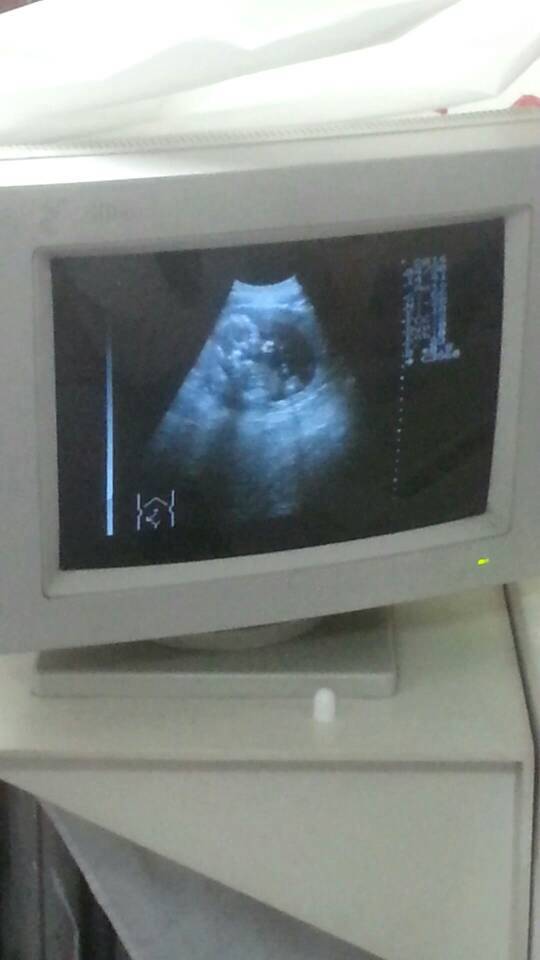

B超有三个小白点,是小鸡鸡还是脐带 点击展开 匿名用户 2014-05-04 12:04 满意回答 你这是几个月的bc 古飞丹_Dpcr 2014-05-04 12:06 宝宝知道提示您:回答为网友贡献,仅供参考。 相关问题 小孩的小鸡鸡里边有两三个小白点是怎么回事不疼不痒要怎么治 小孩的小鸡鸡里边有两三个小白点是怎么回事不疼不痒要怎么治 怀孕七个月做B超会把脐带看成小鸡鸡么?前几天做B超 大夫说是男孩 准确率有多少啊>?